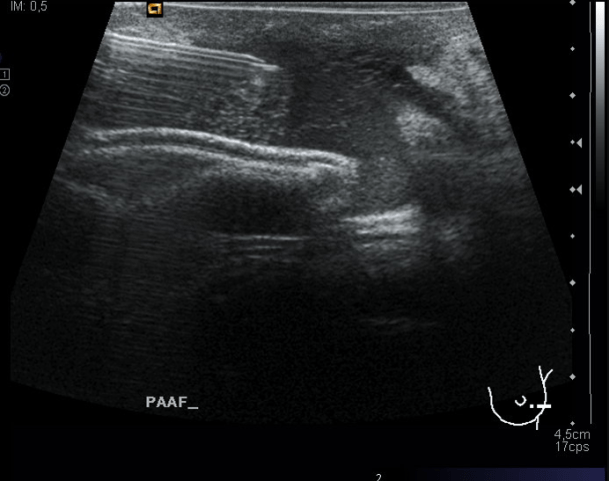

Es muy habitual que lxs pacientes que vienen con sospecha de hiperparatiroidismo, ya vengan diagnosticados con alguna prueba de Medicina Nuclear, como es una Gammagrafía con tecnecio 99m, y la ecografía sea una técnica de confirmación, de guía de punción y prelocalización quirúrgica, que en ocasiones, certificaremos en el mismo quirófano con una ecografía intraoperatoria la resección del tumor.

Las medidas tanto en transverso como en longitudinal, imagen 3 y 4 son importantísimas, hemos hablado anteriormente que la medida tiene relación directa con el diagnóstico diferencial de estas patología tumorales, y como no, la vascularización, que la ves en la imagen número 5 y que está aumentada, usaremos doppler color, imagen 5, y doppler power, imagen 6.

La ecografía muestra un tiroides multinodular, porque tiene otros tipos de imágenes nodulares al margen de la lesión estudiada. Adyacente al LTD y en contacto con la carótida común se observa una lesión nodular, sólida, no es anecoica ni tiene este componente, por tanto se considera sólida, hipoecogénica, que mide 10 x 9 mm y que por su localización y morfología es compatible con un adenoma de paratiroides inferior derecha, anatómicamente suelen ser 4, dos por lóbulo, una en polo superior y otra en el inferior…Hasta el próximo Post.